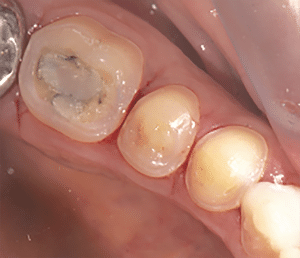

On réalise ensuite les préparations postérieures. La figure 7a est la vue initiale, la 7b la vue occlusale des préparations et la 7c la vue latérale des préparations.

Fig.7a, b, c : Préparations postérieures.

Fig.7b.

Fig.7c.

La préparation des overlays molaires consiste à retirer les anciennes préparations, à faire un biseau périphérique total sur 1-2 mm de hauteur et à hybrider, si nécessaire, les tissus dentinaires. Le biseau va permettre de créer un dôme de compression au niveau de la dent (ce qui va la renforcer), une stabilité de la pièce prothétique, un axe d’insertion unique et de mieux gérer la transition optique et esthétique (il évite d’avoir l’impression que la restauration a été « posée » sur la dent, comme un chapeau). Dans notre cas, on sait que l’augmentation de DV nous a permis de gagner 1 mm. Il n’y a donc pas besoin de réduire au moyen de la fraise la face occlusale, faisant plus de dégâts en quelques secondes que l’usure en plusieurs années…

La préparation des veneerlays est celle d’une facette sur la face vestibulaire et celle d’un overlay sur la face occlusale. Toutes ces préparations sont minimes et s’effectuent dans l’émail. Elles sont ensuite polies pour ne laisser aucune arête vive. Dans notre cas clinique, les veneerlays étaient faits « naturellement » par l’usure qui a réduit la face vestibulaire en laissant un bandeau d’émail périphérique en cervical. Il a été décidé de passer les points de contact car il y avait des débuts de déminéralisation amélaire en proximal. Sans cela, on les aurait conservés.